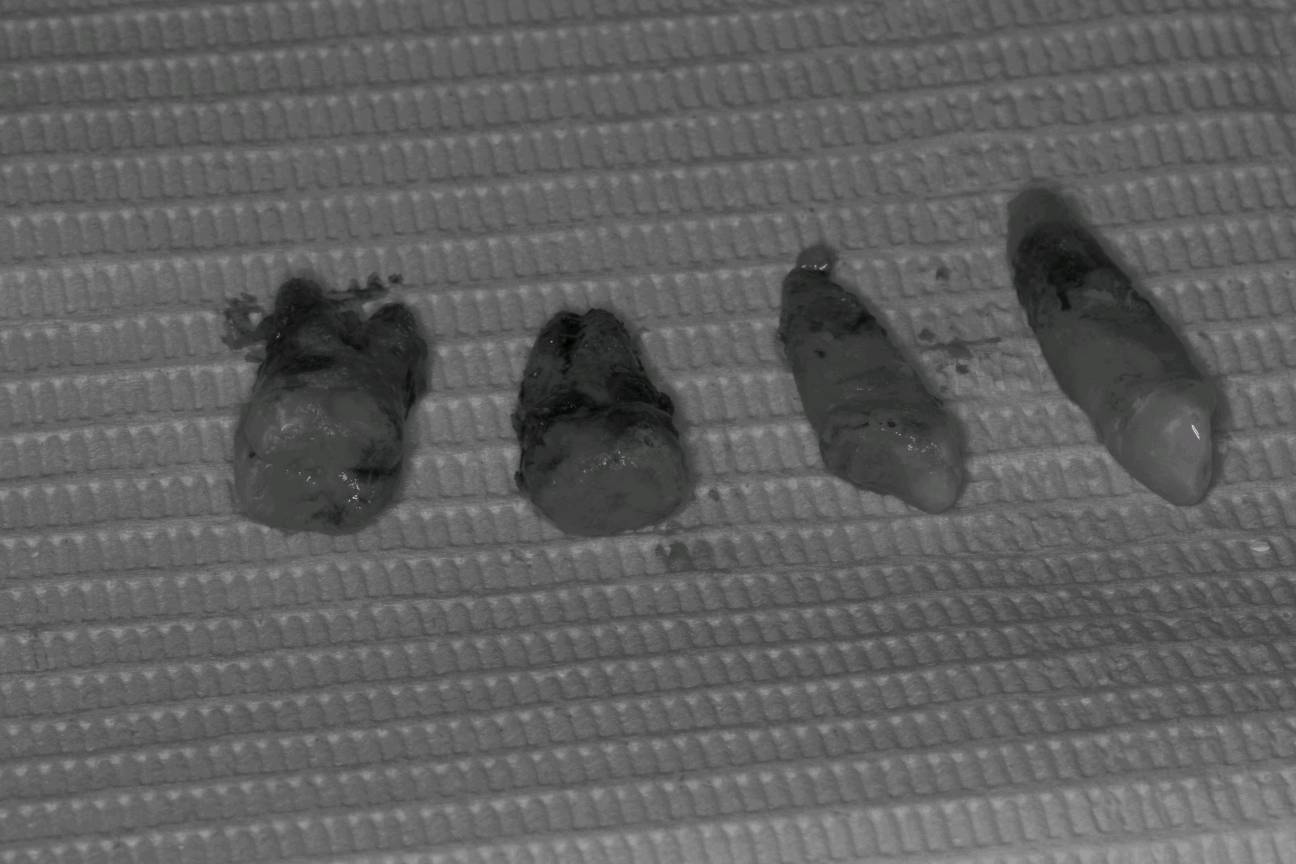

治疗计划:1拔除无法保留的牙齿。2牙槽骨吸收至根尖2/3以上的患牙进行根管治疗。3分次进行牙周刮治。4缺失牙修复。5定期维护